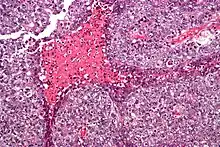

| Micrograph of an embryonal carcinoma showing its typical features – prominent nucleoli, marked nuclear atypia, necrosis, and nuclear overlap. H&E stain. | |

The microscopic features include: indistinct cell borders, mitoses, a variable architecture (tubulopapillary, glandular, solid, embryoid bodies – ball of cells surrounded by empty space on three sides), nuclear overlap, and necrosis.